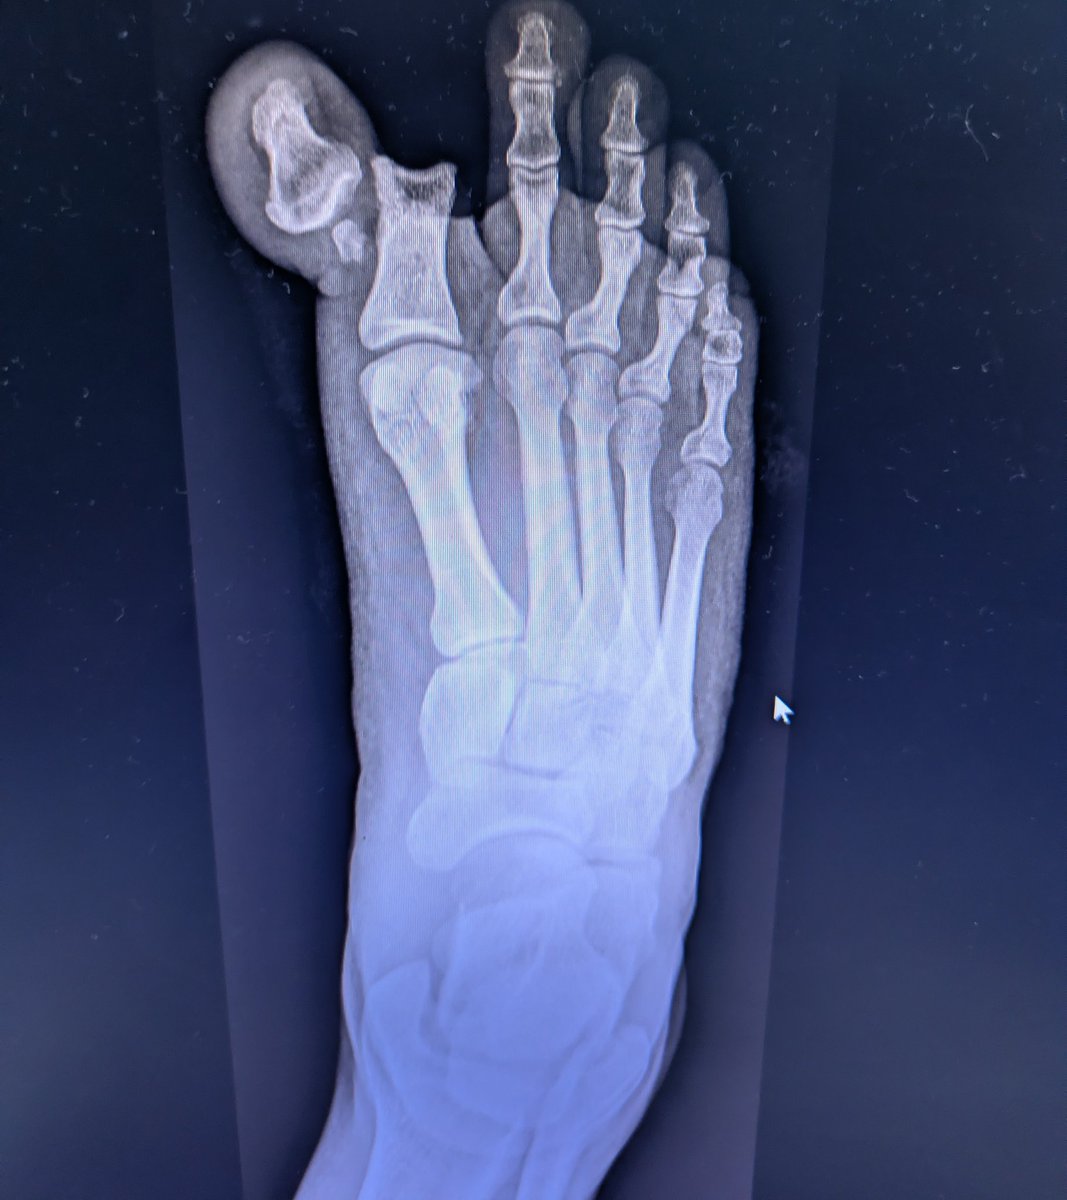

Christmas Day in ED: A gentleman, festive spirits, commando roll, and one dislocated toe. Definitely a mistoe-ltoe moment 🎄 Merry Christmas all — enjoy the festivities, but maybe skip the stunts. Sam Ghali, M.D.